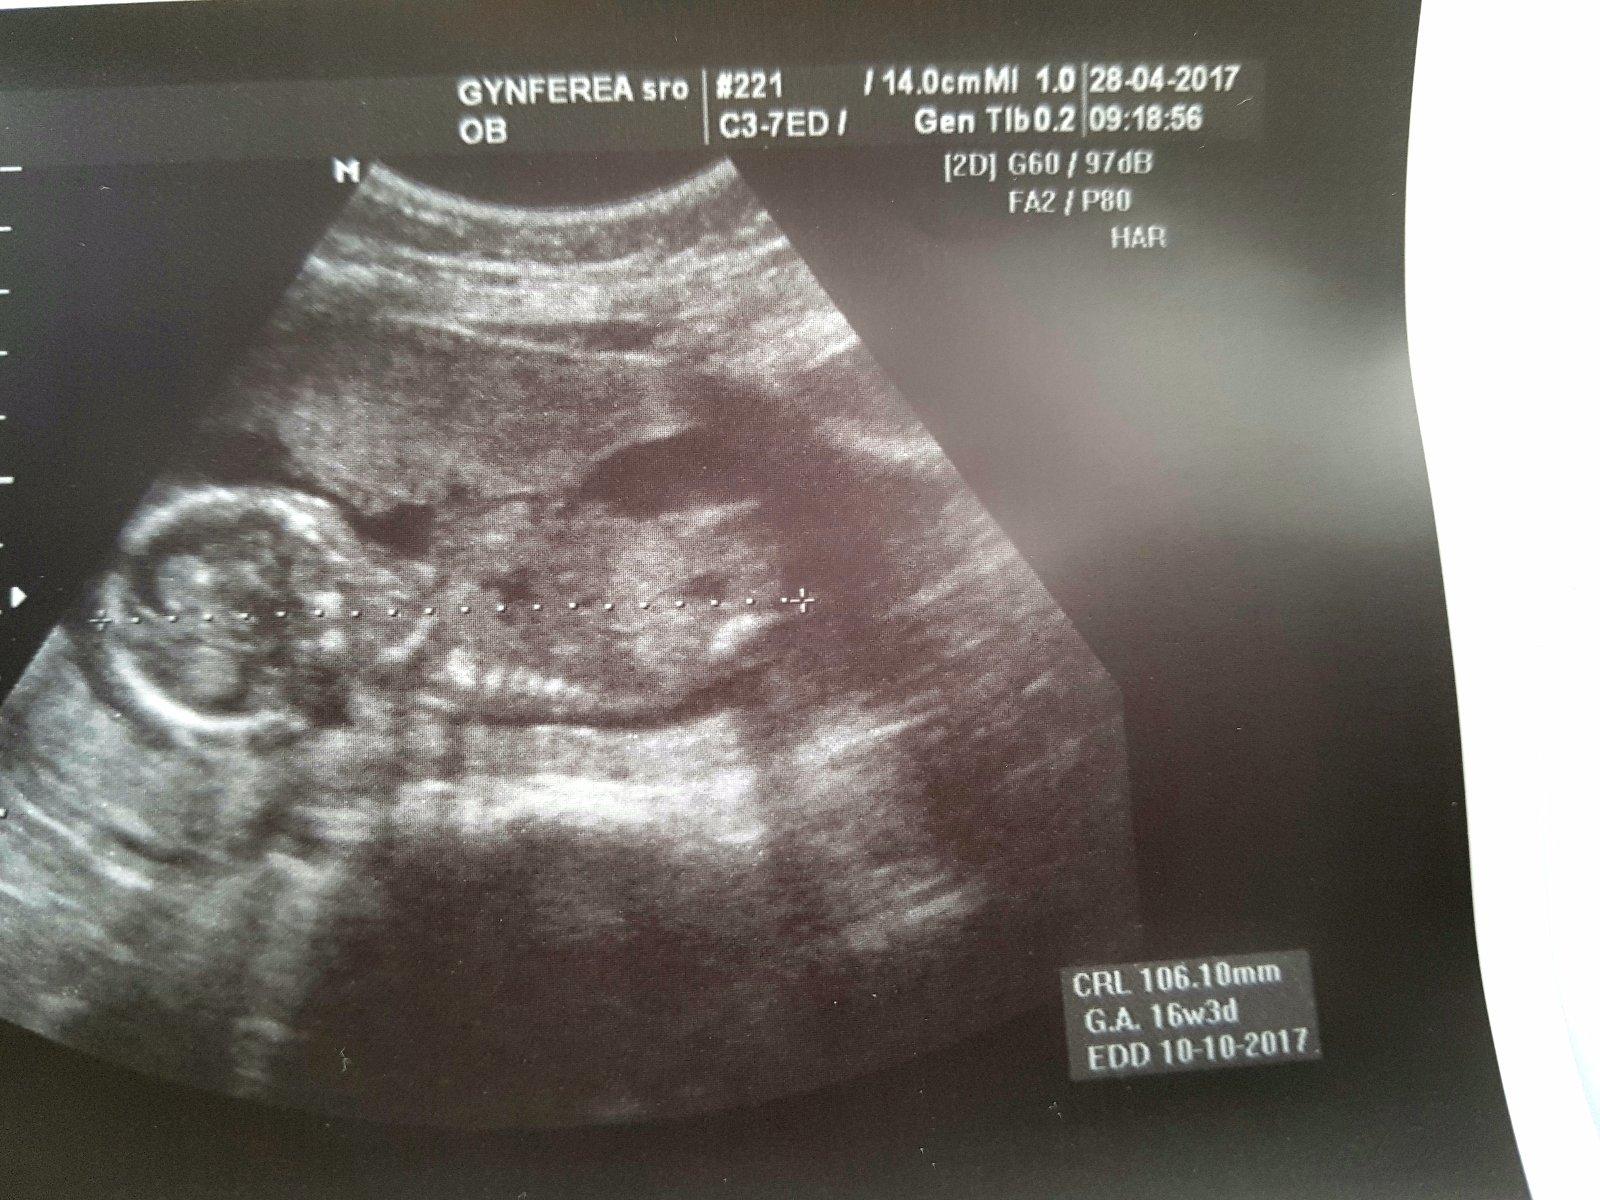

A este foto z posledneho sona .